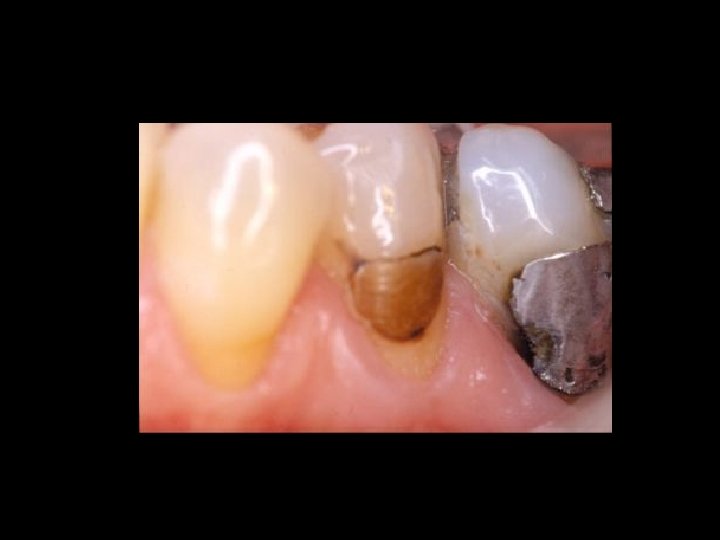

Responsabilità Garanzia di mezzi Ø Garanzia di risultato Ø Scelta del tipo di trattamento Ø Ø Condizioni denti Ø Condizioni delle mucose Ø Condizioni delle ATM Ø Preparazione dei denti pilastro Ø Prospettive di risultato estetico Ø Prospettive di risultato nel tempo Ø Caratteri del manufatto